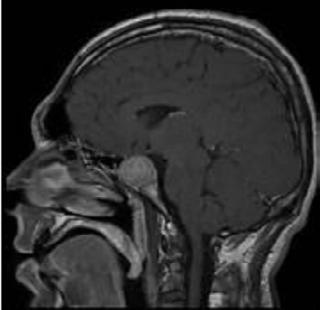

El diagnóstico se realiza, inicialmente clínico y se confirma con estudios de laboratorio y con estudios de imagen.

El diagnóstico clínico se basa en la presencia de las alteraciones clínicas ya mencionadas mientras que el diagnóstico de laboratorio buscará la producción hormonal en exceso. El diagnóstico por imagen se realiza a través de una resonancia magnética con medio de contraste, específicamente para la región hipofisaria.